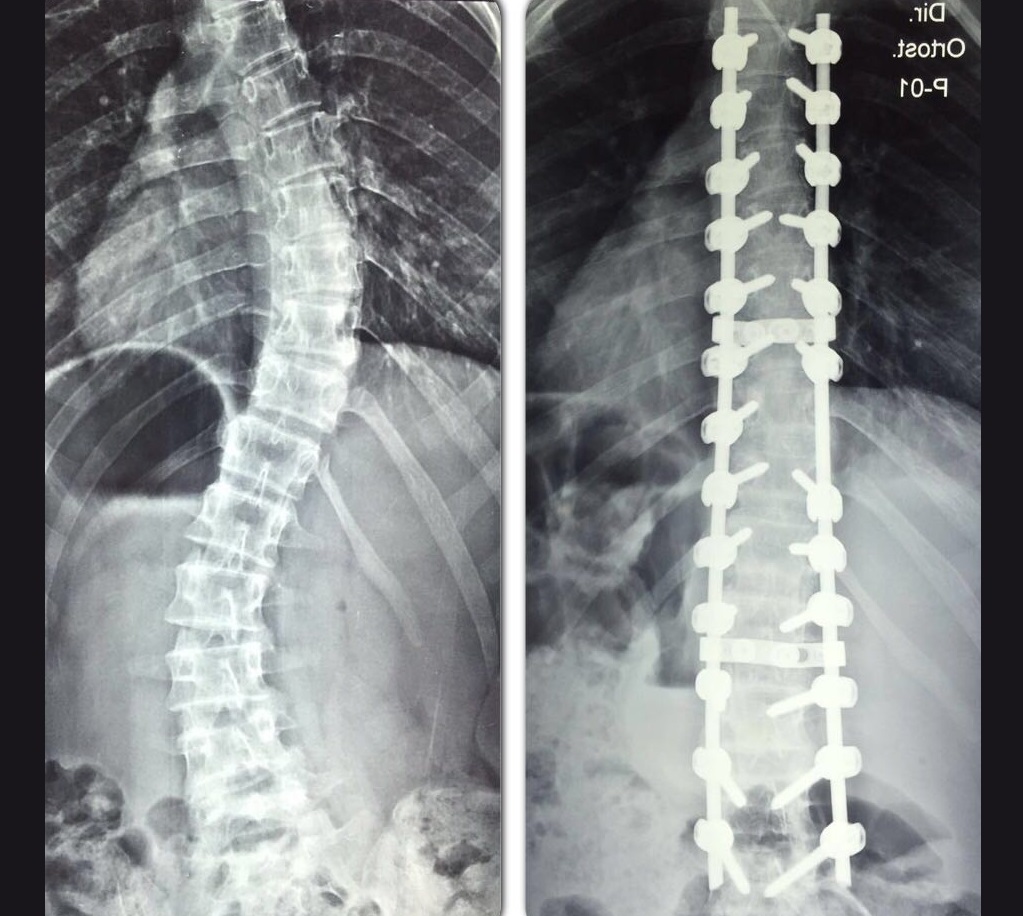

![]() |

| Correção da curvatura da coluna vertebral de alagoana melhorou qualidade de vida de alagoana (Crédito: Cortesia/Arquivo pessoal) |

Com o filho próximo de completar 18 anos, em dezembro de 2013, Anna aproveitou um convênio da empresa onde trabalhava e passou por uma cirurgia para corrigir a curvatura de 84 graus da coluna vertebral. “Tive mesmo de fazer a cirurgia e não voltar mais, mas o procedimento foi bem sucedido”, lembrou a alagoana portadora de escoliose idiopática - adquirida entre 0 ano e a maturidade.

A curvatura não foi completamente corrigida, mas a técnica em enfermagem está satisfeita e fala com muito entusiasmo sobre as mudanças sentidas após a cirurgia. “Não corrigiu 100% porque deixei para operar um pouquinho velha, mas posso dizer que melhorei 99%. Mudou muita coisa, minha autoestima, respiração e a reputação, praticamente quase tudo”, relatou.

“Não exerço minha profissão por conta da minha coluna. Não posso pegar muito peso porque tenho 18 parafusos e duas hastes na coluna. Então no momento não trabalho”, finalizou a alagoana, que é a única dos oito irmãos portadora de escoliose na família.

| Procedimento cirúrgico corrigiu quase toda a curvatura da coluna vertebral de Anna Honório da Silva (Crédito: Cortesia/Arquivo familiar) |

Consta também no site do ortopedista que o procedimento cirúrgico da escoliose tem como objetivo diminuir a curva e evitar a progressão da deformidade, que, se chegar a níveis acima de 70°, pode diminuir o espaço para os pulmões e o coração, comprometendo o sistema cardiopulmonar. Metade das cirurgias utiliza parafusos, ganchos e hastes metálicas para manter o alinhamento da coluna.